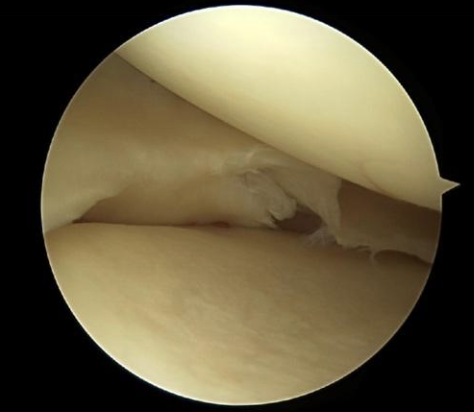

Illustraties van een meniscuscheur tijdens een kijkoperatie:

Flapcompent